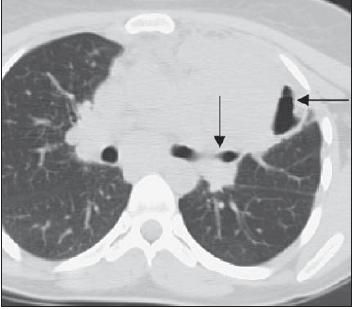

The patient's chest radiograph showed a large left suprahilar mass with cavitation (Figure 1). This was confirmed by a CT scan that showed a large area of consolidation, with an air bronchogram in the left upper lobe and an air-fluid level in the lateral part of the consolidation (Figure 2).

Figure 2 – This CT scan shows a large area of consolidation, with an air bronchogram in the left upper lobe (arrow) and an air-fluid level in the lateral part of the consolidation (arrow).